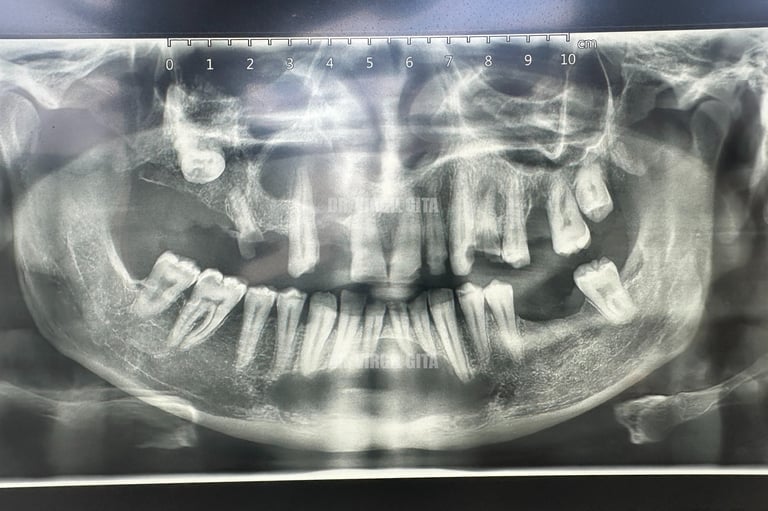

Se deceleaza imagistic o formatiune tumorala radiotransparenta, de mari dimensiuni, localizata la nivelul intregului grup frontal mandibular.

Dupa examenul clinic si imagistic se pune diagnosticul prezumtiv de formatiune tumorala chistica (chist radicular de mari dimensiuni). Se intervine chirurgical realizandu-se extractiile dintilor cauzali, irecuperabili, rezectii apicale a dintilor implicati chistic, care au fost tratati endodontic in prealabil. Piesa operatorie a fost trimisa catre examenul histopatologic, diagnosticul fiind chist radicular fara atipii.